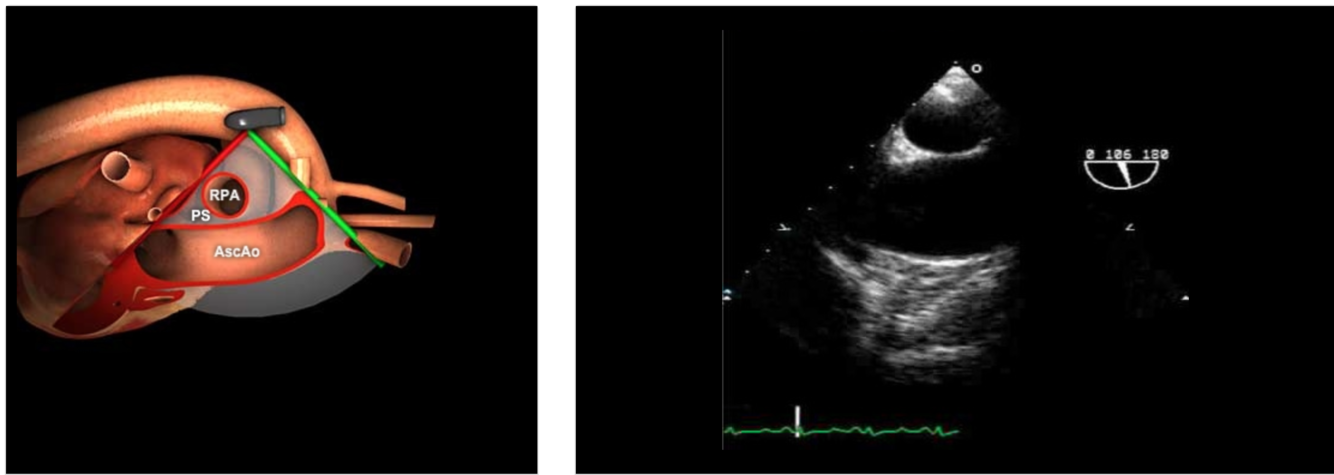

Withdraw the probe to bring the right pulmonary artery in view

Decrease omniplane angle slightly by 10-20° to make the aortic wall symmetric

How do you obtain the ME Ascending Aorta in Short Axis?

Insert the probe to the ME, sector depth 10-12cm, angle 0°

From ME AV SAX (30°), withdraw probe (ascending aorta SAX), rotate the omniplane angle back to 0° (Anteflex a little bit)